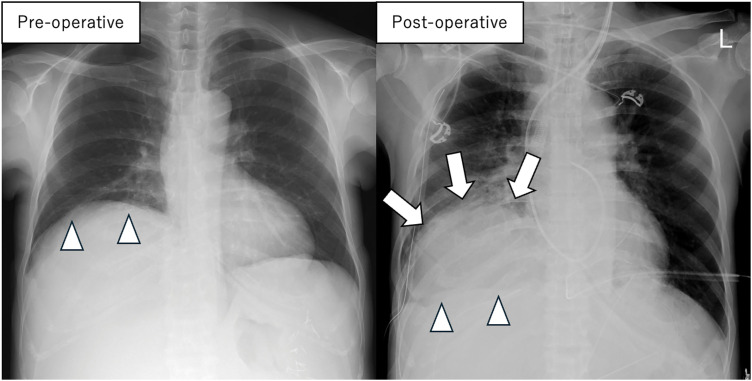

Case presentation: A female patient in her 40s with a history of autosomal dominant polycystic kidney disease presented with progressive liver cyst enlargement (Gigot type III, Qian classification Grade 4), which led to decreased activities of daily living and intracystic hemorrhage. The patient underwent a deceased-donor liver transplantation. During mobilization of the liver from the right side of the diaphragm, the patient experienced sudden onset of pneumothorax. Incision of the diaphragm revealed a cystic structure containing a hematoma, suggesting pneumatocele formation. The pneumatocele was not resected during the ongoing operation; instead, thoracic drainage was performed as the primary intervention. Postoperatively, no air leakage was observed, and the thoracic drain was successfully removed on POD 12. The pneumatocele, which measured approximately 10 × 10 × 7 cm, showed no signs of infection, and was monitored without additional surgical intervention. On POD 19, a fever prompted further evaluation, and CT-guided cyst aspiration for culture was performed, which revealed no evidence of infection. Acute T-cell-mediated rejection was observed on POD 27, and a steroid pulse was administered, but even after that, the pneumatocele gradually decreased in size without any signs of infection.